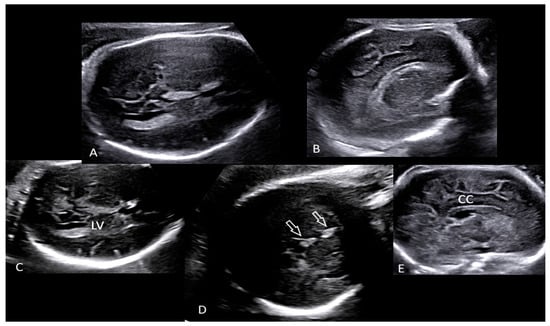

2. The Case

- Rac, M.W.F.; Bryant, S.N.; McIntire, D.D.; Cantey, J.B.; Twickler, D.M.; Wendel, G.D., Jr.; Sheffield, J.S. Progression of ultrasound findings of fetal syphilis after maternal treatment. Am. J. Obstet. Gynecol. 2014, 211, 426.e1–426.e6. [Google Scholar] [CrossRef]

- Lawrence, N.L.; Twickler, D.M.; Peters, M.T.; Sanchez, P.J.; Wendel, G.D. Fetal Syphilis: Correlation of Sonographic Findings and Rabbit Infectivity Testing of Amniotic Fluid. J. Ultrasound Med. 1993, 2, 97–101. [Google Scholar]

- Araujo Júnior, E.; Santana, E.F.M.; Rolo, L.C.; Machado Nardozza, L.M.; Moron, A.F. Prenatal diagnosis of congenital syphilis using two- and three-dimensional ultrasonography: Case report. Case. Rep. Infect. Dis. 2012, 2012, 478436. [Google Scholar] [CrossRef]

- David, M.; Hcini, N.; Mandelbrot, L.; Sibiude, J.; Picone, O. Fetal and neonatal abnormalities due to congenital syphilis: A literature review. Prenat. Diagn. 2022, 42, 643–655. [Google Scholar] [CrossRef] [PubMed]